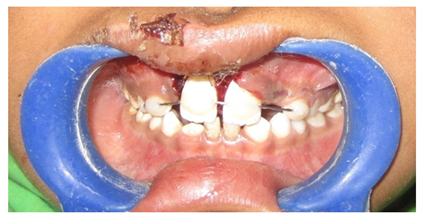

A 10year old boy reported to the department of Pedodontics with a chief complaint of missing upper front tooth and gave a history of fall from bike while 5 days back. They had been to pediatrician for the lacerated lip and got it sutured. Parents had kept the avulsed tooth in paper without knowledge of reimplantation of the same tooth. Patient had no relevant medical and family history. On examination swelling and suture was present on upper lip, lacerated gingiva with healing socket in 11 regions. 21 was intact, vital and non mobile. (Figure 1) (Figure 2) On examination of avulsed tooth 11, it was found to have open apex (Figure 3). On intraoral radiographic examination, no fracture was seen with alveolar bone (Figure 4). Thus avulsed tooth was cleaned and debrided with soft pumice prophylaxis, gentle scaling was done to remove ligament remnants. It was then placed in 1.23% sodium fluoride for 15minutes. Extraoral endodontic therapy was also done using retrograde filling of MTA (Figure 5). Local anesthesia was administered and socket was cleaned, curetted and irrigated to remove clot and debris and 11 was slowly reimplanted in socket. Orthodontic wire – composite splinting was done for 4weeks as the dry storage was more than 60minutes (Figure 6). Systemic antibiotics amoxicillin and doxycycline were prescribed for 5days. The patient was recalled after 1 month and splint was removed. No mobility was present. Again patient was recalled after 2months to check the condition (Figure 7). Again patient was recalled after 6months; tooth had slightly discolored but was not mobile and maintained the space (Figure 8). Patient was happy and contended with the reimplantation of his own tooth without disturbing his original look.

Figure 1 Extra oral photograph.

Figure 2 Intraoral pre-operative photograph.